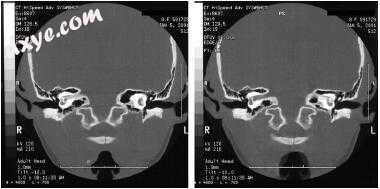

图-11. 影像学表现为左侧岩尖炎。 A,颞骨骨骼计算机断层扫描显示左颞骨岩尖炎。注意岩骨顶端的浑浊与骨质隔膜(星号)的破坏。在这个对比研究中也可以看到颈动脉管的裂开和岩骨颈动脉的狭窄(箭头)。 B,轴位非对比增强T1加权磁共振成像(MRI)显示乳突浑浊(星号)。与右侧看到的亮脂肪信号相比,左侧岩尖也是不透明的(箭头)。注意左侧颈内动脉狭窄口径(ICA;短箭头)与右侧ICA(箭头)相比。 C,轴向造影增强T1加权MRI在左侧岩尖处显示低信号,周边对比度增强(黑色箭头)与炎症一致。注意左侧ICA的窄口径(短箭头)与右侧的ICA(箭头)相比较。 D,冠状位造影增强T1加权MRI在左侧岩尖部显示低信号,周边对比度增强(黑色箭头)。注意增强毗邻岩尖的硬脑膜和颞叶(白色箭头)。 E,治疗前患者的MR血管造影(MRA)显示左侧岩石ICA变窄(箭头)。 F,随访MRA显示缩小后的ICA正常口径(箭头)。